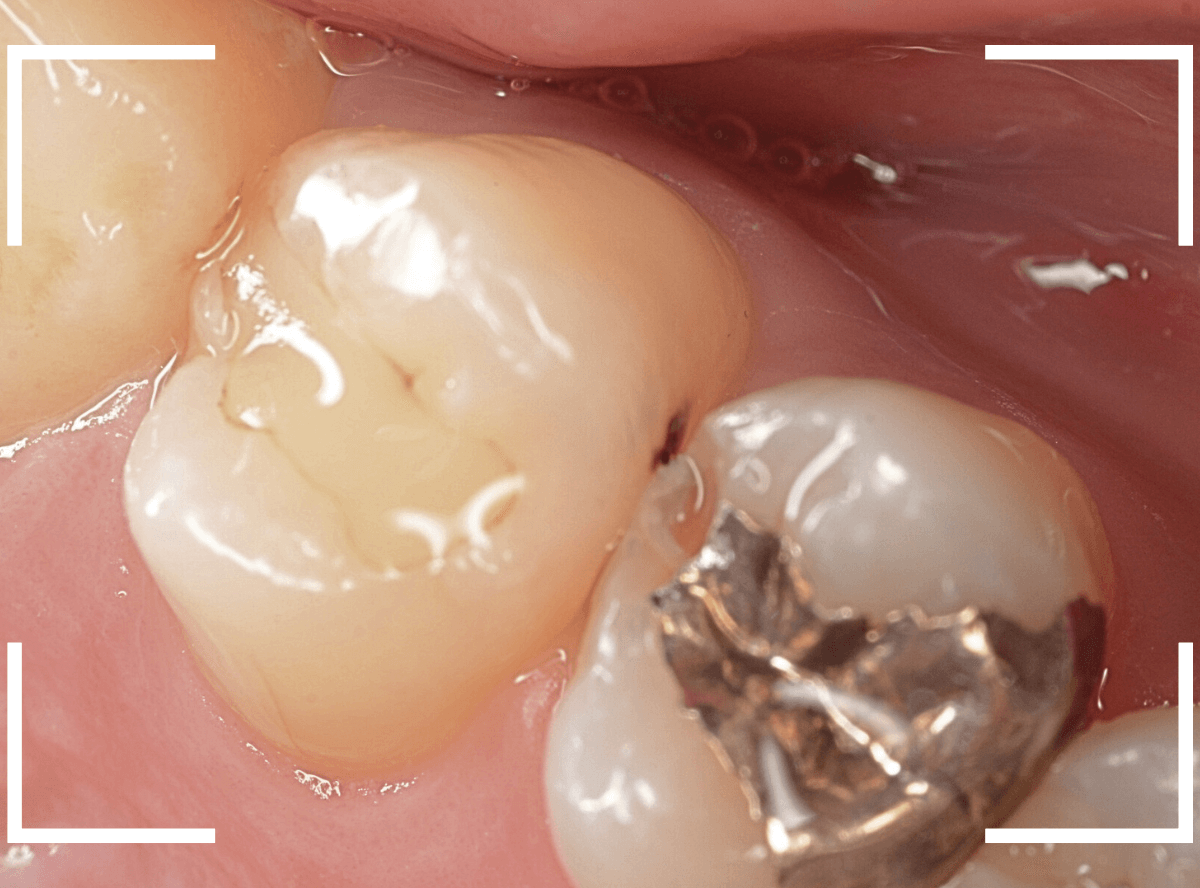

Case.8 大きな虫歯なのに、レントゲンではっきり写らない

こちらも定期検診希望で来院された患者さんです。

お口の中を拝見すると、明らかに虫歯がありました。

3本虫歯になっており、特に中央の小臼歯はかなり大きな虫歯になっているのが予想されます。

治療前にレントゲン写真で虫歯の大きさを確認するつもりが・・・あまりはっきり写ってきません。

患者さんに状況を説明して、歯を少しずつ削りながら虫歯を確認する事になりました。

まず、一番大きな虫歯と思われる部分を小さく削って確認します。

予想通り、虫歯が見えてきました。

隣りの奥歯と一緒に虫歯の治療を進めます。

色が染まっているところがまだ虫歯が残っている部分です。

2本とも、虫歯を全て取り切りました。

特に手前の歯はかなり広めの虫歯になっていました。

最終的に、手前の虫歯の除去も終わったところです。

手前の歯の虫歯は中央の歯まで達していました。

このように明らかに大きな虫歯があると診断されるような状況でも、レントゲン写真でうまく診断できない場合もあります。